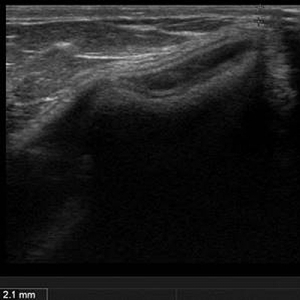

- 見た目には大きな変化がないものの、エコー検査では皮膚からバッグまでの距離が、たった2.1mmと判明

こちらの50代の女性は「バッグを入れた胸が硬く、右胸の少し赤くなっている部分がしこりのように触れる」とお悩みでした。術前のエコー検査では、豊胸シリコンバッグがリップリングを起こしており、しこり状の部分は縁が角になっており、皮膚からの距離はわずか2.1mmしかないことがはっきり見て取れました。